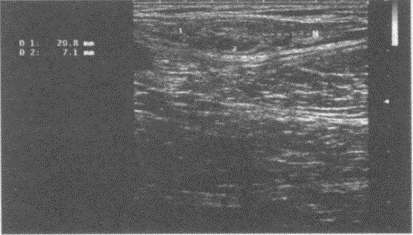

颈部扫查:请指出图1中测量为0.31cm的管径,彩图85(1)所指,彩图85(2)PW取样容积取样处分别是颈部哪条血管()。

A.椎动脉

B.甲状颈干动脉

C.颈总动脉

D.锁骨下动脉